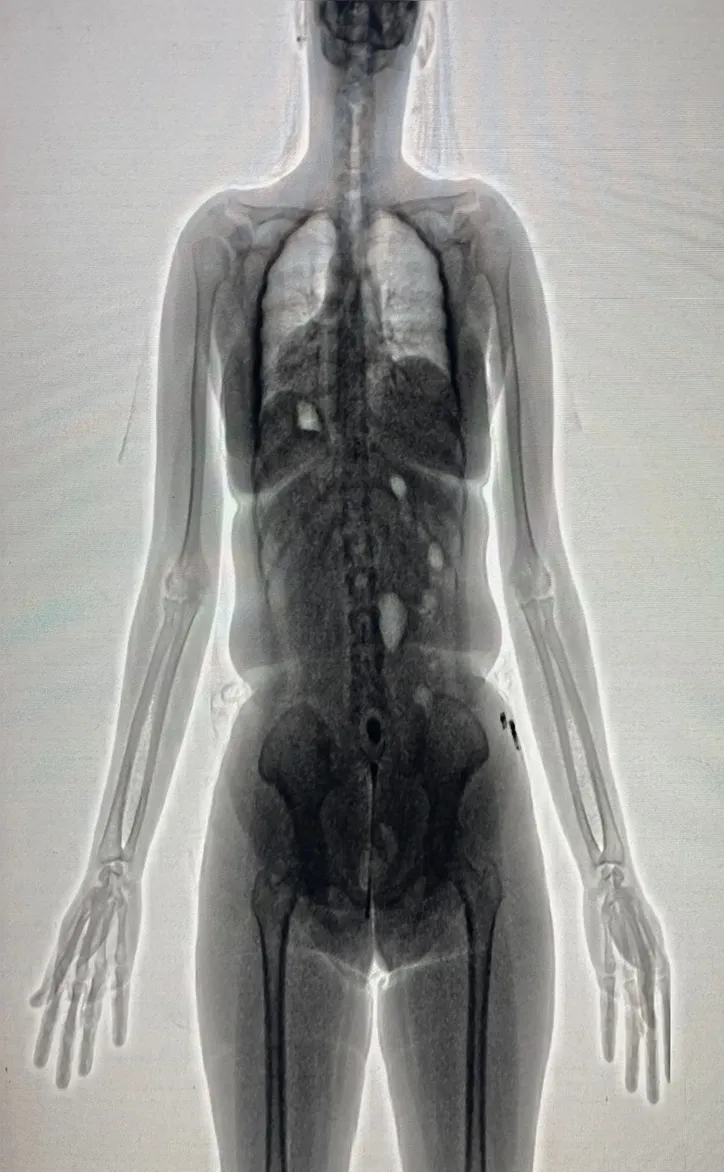

De acordo com a Secretaria de Administração Penitenciária e Ressocialização (Seap), a visitante, companheira de um dos internos, transportava cerca de 20 gramas de uma substância semelhante à maconha escondida nas partes íntimas. A tentativa foi descoberta com o auxílio do equipamento BodyScan, que apontou a presença de um objeto estranho por meio das imagens captadas.

A ocorrência foi informada à Direção do Conjunto Penal, que determinou o arquivamento das imagens do BodyScan para fins administrativos e legais. Em seguida, a visitante foi encaminhada à Delegacia de Polícia de Barreiras, sob escolta da Polícia Militar, seguindo o protocolo adotado para situações dessa natureza.